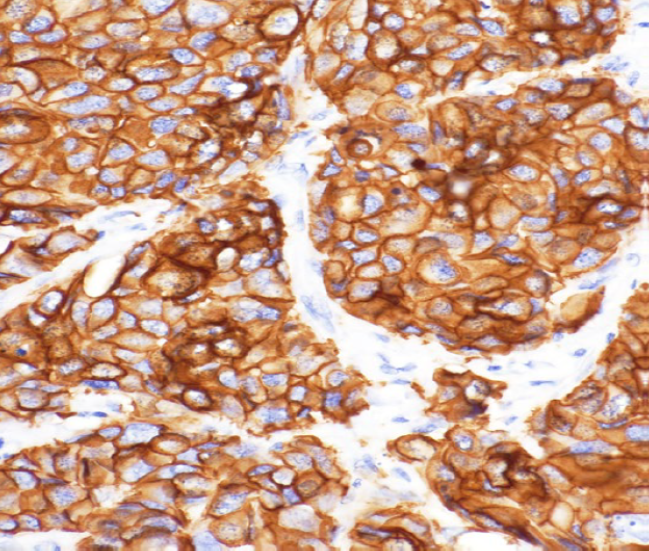

02 12轴校正,让色彩还原更精准

色彩还原精准,一直让DP相机家族广受赞誉。DP75将该技术进一步提升,将色彩空间划分为12个区域独立校正,让各种常见的病理染色标本都得到真实的色彩再现。

样品:HE染色结肠